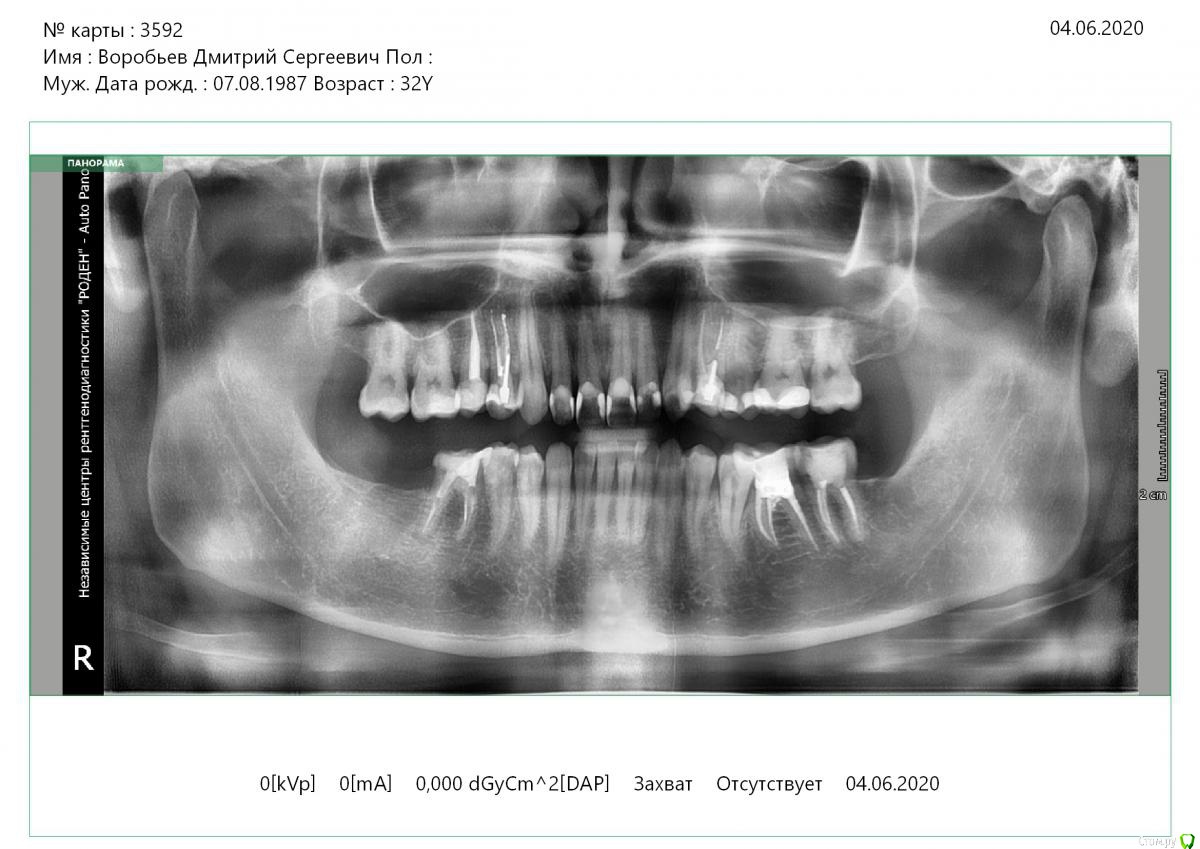

Vords Опубликовано 11 июня, 2020 Поделиться Опубликовано 11 июня, 2020 (изменено) Доброго вечера, профессионалы. Прошу у Вас помощи. Буду очень благодарен за консультацию. 3 недели назад появились боли в в жевательных зубах (около 37 и 36 зубов). В виду того, что боли были достаточно серьезные, а врач, у которого я лечился ранее не мог меня принять из-за пандемии - пришлось идти в городскую поликлинику. По результатам похода был поставлен диагноз пульпит 37 и глубокий кариес 36. На 36 поставили пломбу - 37 успешно депульпировали. На этом история 37 зуба закончена. С 36 после постановки пломбы начались дикие ночные боли и боли при накусывании. На повторном приеме был поставлен диагноз пульпит 36 - поставлено лекарство для умертвления нерва. После этого боль при накусывании прошли. В следующий прием пришел на чистку каналов и пломбировку. Во время этой процедуры я вдруг ощутил совершенно дикую боль (как выяснилось потом - в этот момент и произошла перфорации в области фуркации). Врач ничего не сказал - просто поставил метапекс и запломбировал каналы. В этот момент начались боли при накусывании. а потом постоянная тянущая боль. Продолжалось это около 3 дней - я пошел в другую стоматологию где мне сделали рентген и с подозрение на перфорацию отправили на КТ. По результатам КТ перфорация была подтверждена. С КТ я пришел в городскую стомотологию где мне предложили закрыть перфорацию цементом (pro что-то там - не могу сказать точно). Закрыли ее во вторник на этой неделе. Сегодня восстановили коронку и поставили световую пломбу. Беда в том, что боль при накусывании и "нытье" с этой стороны так и не прошли. По словам стомотолага гос клиники - боль при накусывании из-за метапекса и когда он рассосется - боль пройдет. (до 6 месяцев). Я прилагаю рентген (ужасное качество), фото КТ и ссылку в облако на КТ. Я допускаю, что никто не захочет лезть в облако и тратить свое время на просмотр на КТ (сам не могу разобраться с программой, что бы сделать достойные скрины), но если вдруг у кого-то найдется время - буду очень благодарен. Рентген сделан сразу после пломбировки канала. КТ через 3 дня после этого. В связи с этим вопрос. Возможно ли, что боль при надавливании пройдет если подождать пока рассосется метапекс или это пустая трата времени? Мне стоит ждать какое - то время или в этой ситуации мне поможет только удаление? Благодарю Вас за уделенное время Ссылка на КТ https://cloud.mail.ru/public/44WE/2JeTfXmr2 Изменено 11 июня, 2020 пользователем Vords Ссылка на комментарий

krokomot Опубликовано 11 июня, 2020 Поделиться Опубликовано 11 июня, 2020 Судя по всему у вас в 6м зубе выведен не только метапекс но и гуттаперчевый штифт, скорее всего, если это не исправить боли сохранятся, и что там с коронкой не понятно, на кт сильные тени из-за большого объема рентгеноконтрасного материалла, а прицельный снимок что вы сделали, сделан не поп правилам и на нем сильные искажения, понять трудно что с коронкой. Короче, зуб с перфорацией , выведенным материалом за апексом и гуттаперчей, и при этом еще и беспокоит, прогноз сомнительный. возможно всё можно переделать и всё станет нормально , но это не точно. Вам нужен грамотный доктор эндодонтист. 1 Ссылка на комментарий

Vords Опубликовано 12 июня, 2020 Автор Поделиться Опубликовано 12 июня, 2020 Да прицельный качественный подтвердит наличие штифта за апексом Доброго дня! Сделал прицельный еще один. По нему можно сделать какие-то выводы относительно наличия штифта? Благодарю за уделенное время. Ссылка на комментарий

krokomot Опубликовано 12 июня, 2020 Поделиться Опубликовано 12 июня, 2020 Да есть 2 Ссылка на комментарий